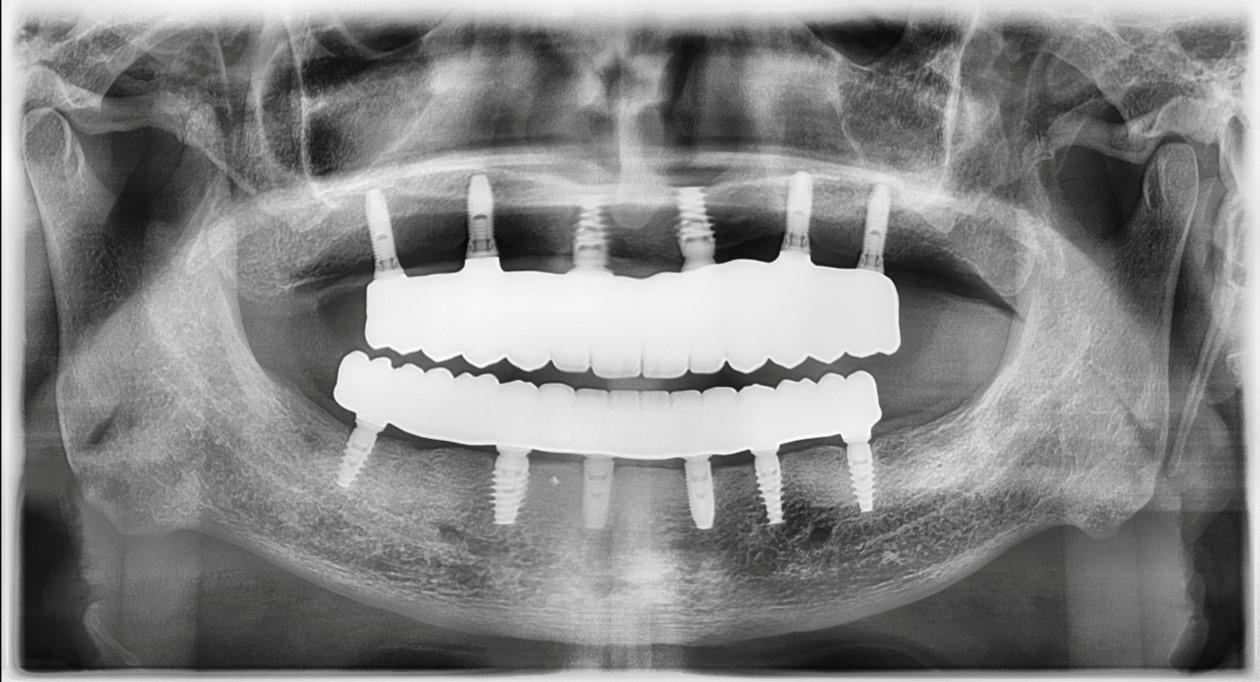

The revolutionary All-on-X (AOX) model-less workflow has become a reality through seamless integration of state-of-the-art technologies: interactive implant planning software, guided surgery systems, intraoral scanning (IOS), advanced 3D printing, and photogrammetry. Our innovative CAD-CAM protocols dramatically streamline the treatment process, reducing appointment frequency, chair time, and prosthetic delivery intervals. We've pioneered multiple digital workflows that ensure precise implant position recording and bite capture for full-arch implant rehabilitation.

- Gain in-depth understanding of stackable guided surgery principles and implementation

- Master new digital techniques for capturing implant positions with absolute precision